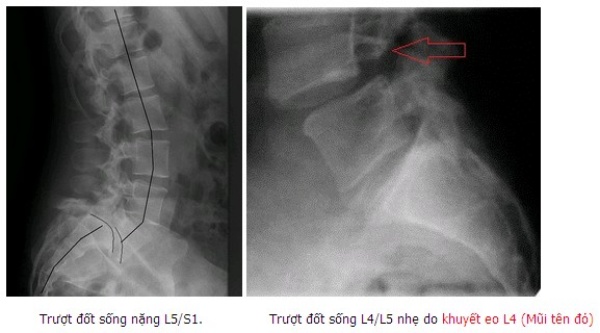

Có nhiều nguyên nhân trượt đốt sống khác nhau như: TĐS do thoái hóa, TĐS do khuyết hở eo, TĐS sau mổ giải ép mở cung sau, TĐS do khối u … Tuy nhiên hay gặp nhất vẫn là TĐS do khuyết hở eo và thoái hóa [1].

Có 2 BN (6,7%) bị TĐS do khuyết eo, 93,3% do thoái hóa. Trượt độ I chiếm 86,7%, còn lại độ II và độ III. Chiều cao đĩa đệm trước mổ trung bình 8,0 ± 2,5 mm (3 – 11 mm). 27 BN (90%) có hình ảnh hẹp ống sống, 03 BN (10%) có hình ảnh hẹp lỗ liên hợp trên phim MRI.

Xquang: Trên phim Xquang cột sống thắt lưng có 93,3% BN bị TĐS do thoái hóa, chỉ có 2 BN (6,7%) bị TĐS do khuyết eo gặp ở bệnh nhân trẻ tuổi. Đánh giá mức độ TĐS theo Meyerding, trượt độ I chiếm 86,7%, còn lại độ II và độ III. Kết quả này tương đồng với một số nghiên cứu khác như: Phan Trọng Hậu trượt độ I là 51,4%, độ II là 41,4%, độ III là 7,2%; Phan Minh Đức có kết quả trượt độ I là 69%, độ II là 30%, độ III là 1%.